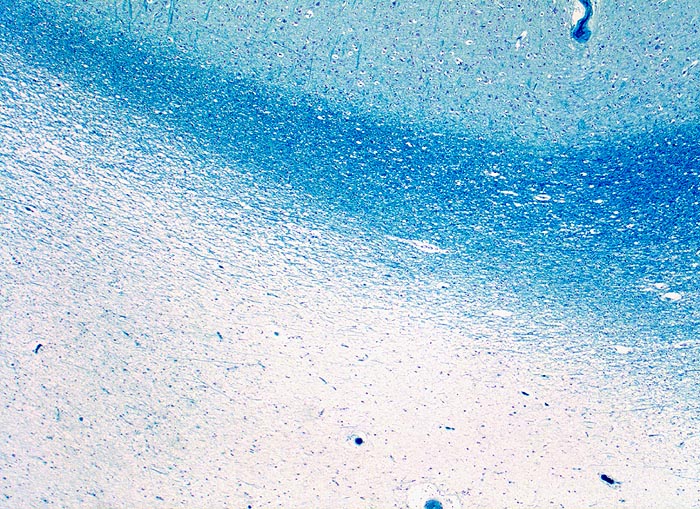

• Alter, scharf begrenzter Entmarkungsherd mit Verlust der blauen Myelinscheiden in der Holmes Luxol Färbung.

• Vollständiger Verlust der Markscheiden (fehlende blaue Farbe) bei erhaltenen Axonen (schwarze Fasern).